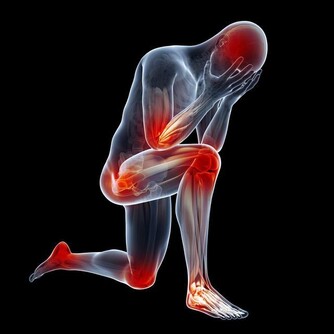

持續肩膀酸疼,需警惕!

肩膀酸疼,是坐辦公室的白領們經常會出現的問題。其實大部分情況也的確是因為長期伏案工作太過於疲勞了。但是如果肩膀酸疼的症狀長期持續而不減緩解。同時還出現了一些其他的並發問題,一定就要提高警惕了。這很可能是肝癌的前兆。

肝癌不應該是肝部腹部會疼麼,為什麼肩膀疼也是先兆呢?

這是由於肝臟本身就有強大的代謝功能,肝癌的表現多種多樣,容易被忽視。肝位於上腹部,肝癌初期並無徵兆,一般人難以察覺,甚至當腫瘤增大至十公分以上時,有的人還是缺乏典型症狀。

當肝臟腫瘤逐步增大,有可能會壓迫附近的橫膈膜,亦可壓著肺部以下的肌肉神經。而這些被壓著的神經正好是連接右肩的神經,就會引發右肩疼痛。所以,當出現反反复复的右肩膀疼痛時,經過適當的治療,症狀未能好轉,要及時檢查肝臟以排除存在的病變。

僅僅是肩膀疼,就判斷是肝出問題了也是太過武斷。如果同時伴有以下這些情況,那就真得注意了。